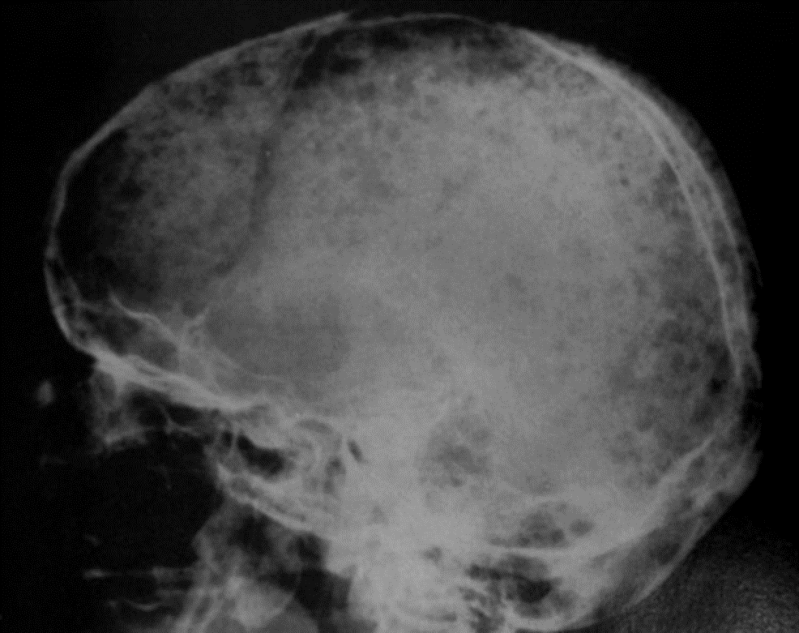

• Radiografía lateral de cráneo .

Lesiones osteolíticas múltiples  de borde no escleroso , tamaño uniforme y homogéneas . Típicamente lesiones en sacabocados .Patrón en sal y pimienta .